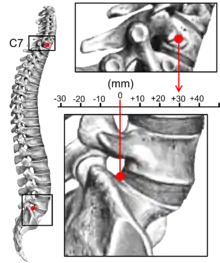

Kyphosis is an abnormally excessive convex curvature of the spine as it occurs in the thoracic and sacral regions.[1][2] Abnormal inward concave lordotic curving of the cervical and lumbar regions of the spine is called lordosis. It can result from degenerative disc disease; developmental abnormalities, most commonly Scheuermann's disease; osteoporosis with compression fractures of the vertebra; multiple myeloma; or trauma. A normal thoracic spine extends from the 1st thoracic to the 12th thoracic vertebra and should have a slight kyphotic angle, ranging from 20° to 45°. When the "roundness" of the upper spine increases past 45° it is called kyphosis or "hyperkyphosis". Scheuermann's kyphosis is the most classic form of hyperkyphosis and is the result of wedged vertebrae that develop during adolescence. The cause is not currently known and the condition appears to be multifactorial and is seen more frequently in males than females.[3]

In the sense of a deformity, it is the pathological curving of the spine, where parts of the spinal column lose some or all of their lordotic profile. This causes a bowing of the back, seen as a slouching posture.